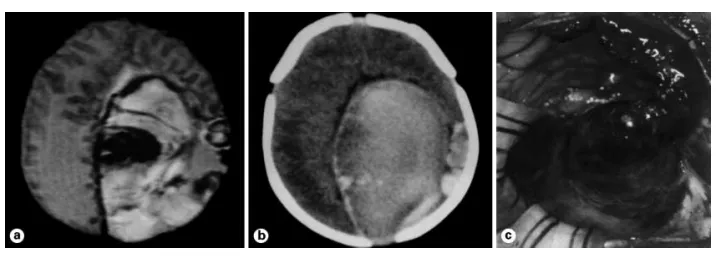

图1.本例为1日龄新生儿,于出生前数日经由产前超声检查诊断为广泛的左侧顶枕叶出血。出生后不久,患儿即呈现深度昏迷状态,伴有瞳孔散大及对光反射微弱。a. 磁共振T2加权像清晰显示血肿,其内包含处于不同降解阶段的血红蛋白产物;未见明确异常的血管结构。b. CT扫描图像:血肿周边的相对低密度区域被解读为超急性期出血。c. 手术中所见:模拟血肿表现的占位性病变,实际为一个高流量动静脉畸形的巨大动脉瘤。术后过程以临床状况的逐渐改善为特点。至5岁时随访,其精神运动发育处于正常水平。